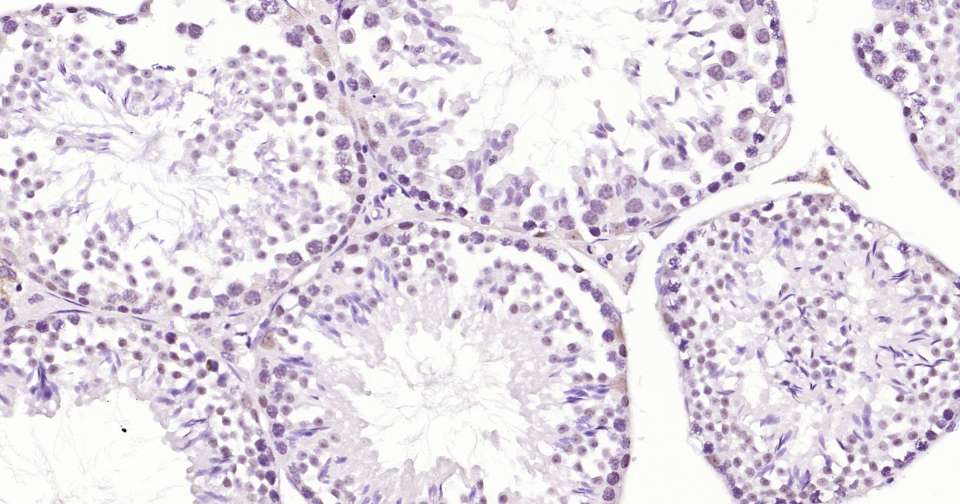

Immunohistochemical analysis of paraffin embedded mouse testis tissue slide using IHC0319 (PARP Kit).

Immunohistochemical analysis of paraffin embedded human testis tissue slide using IHC0319 (PARP Kit).